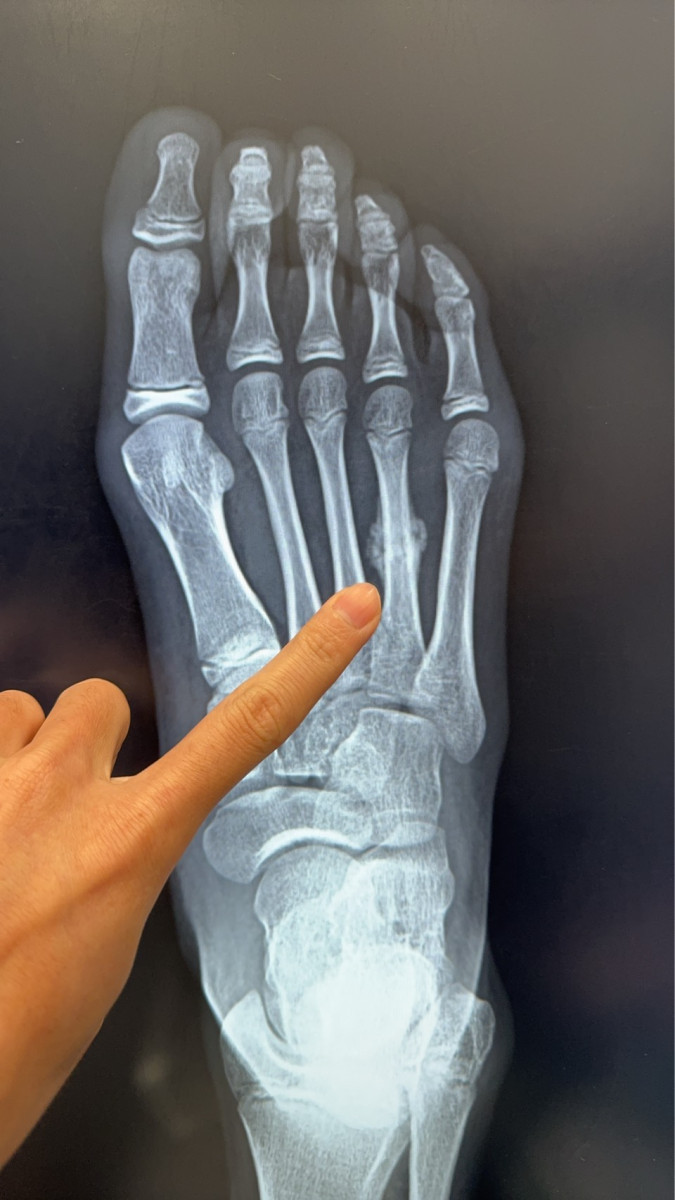

近日,陳建宏骨科診所接獲一名11歲女學童就醫個案,該學童因暑期密集參加田徑與球類訓練,右側腳掌疼痛兩周未緩,檢查後確診為「蹠骨應力性骨折」,且已出現癒合跡象。

11歲女學童右側腳掌「蹠骨應力性骨折」,且已出現癒合跡象。